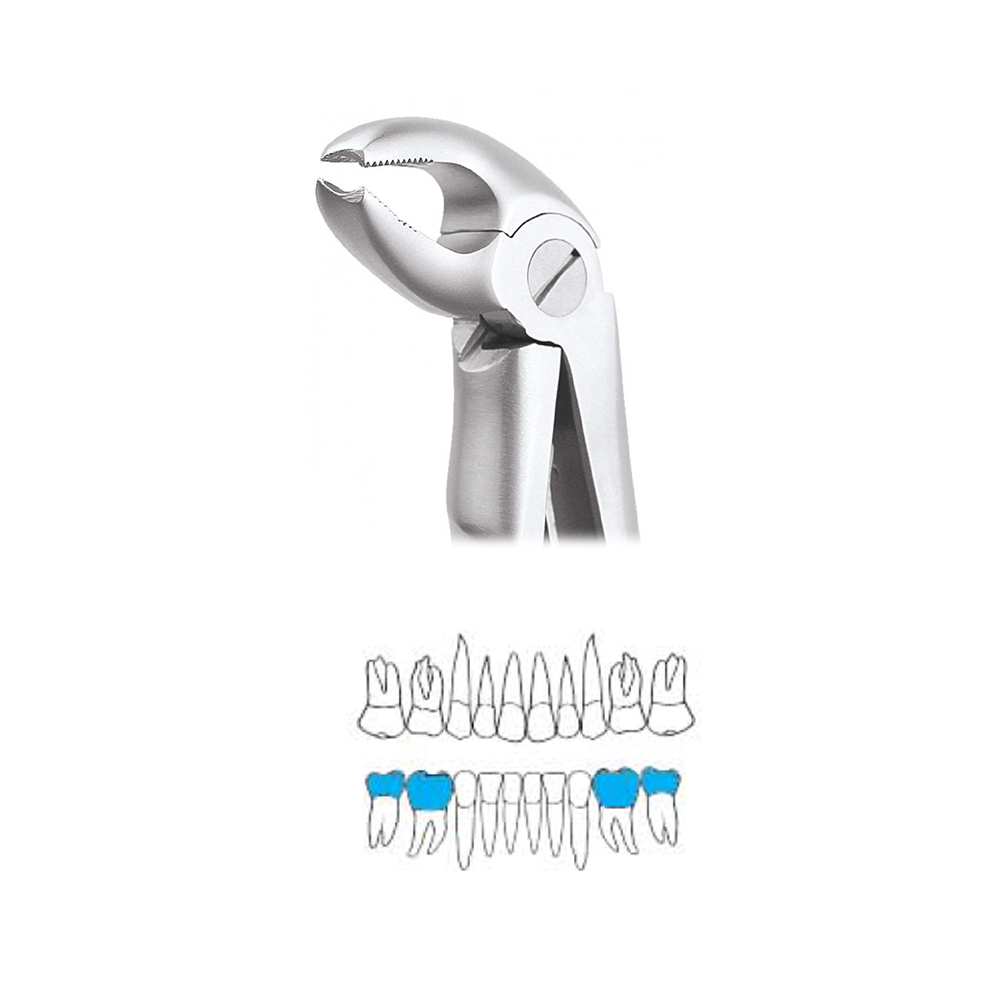

Pedo Extraction Forceps: These specialized forceps are designed to extract deciduous (baby) teeth gently. They have smaller, anatomically adapted beaks that fit comfortably around the smaller roots of baby teeth, reducing the risk of trauma during extraction. The handles are designed for easy grip and better control, ensuring a safe and efficient extraction process.

Pedo American Forceps: These forceps are designed to grip and extract deciduous teeth that are mobile or need removal. They have unique beak designs that cater to the varying shapes and sizes of baby teeth, providing a secure hold for extraction while minimizing any discomfort for the child.